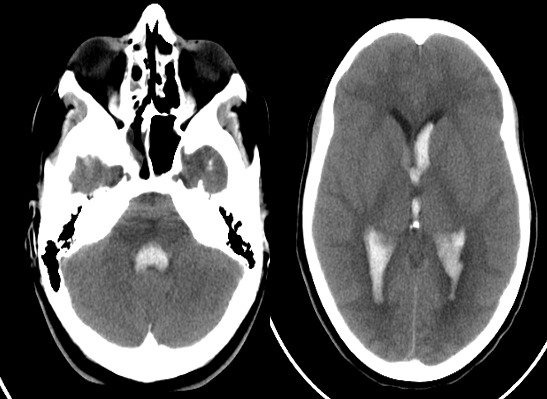

- Blood, being denser than CSF, has settled in the posterior horns of the lateral ventricles as these areas are dependent fluid-filled portions in the supine position.

Intra ventricular hemorrhage